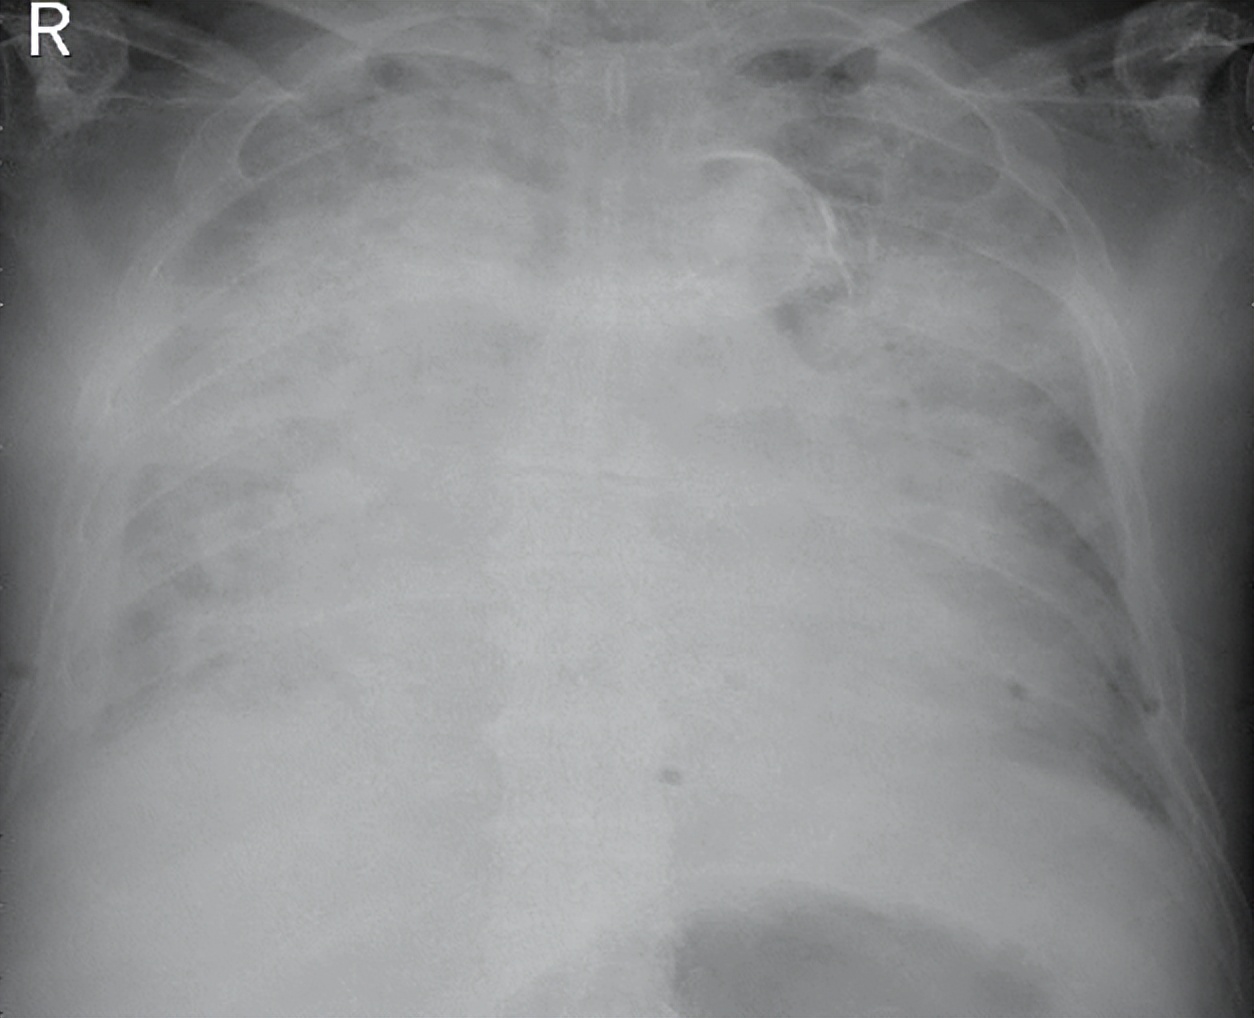

病程进展,症状加重……行气管插管机械通气,继续行抗感染治疗

治疗期间患者疾病进展,低氧血症及呼吸窘迫症状逐渐加重,氧合指数进行性下降,肺部病灶短期进展(图3)。因氧合无法维持,患者精神状态转差,于2023年1月31日胸片检查后行气管插管机械通气(图4),继续给予特治星(哌拉西林他唑巴坦)抗感染,辅以化痰、抗心衰、保肝等治疗。

图3